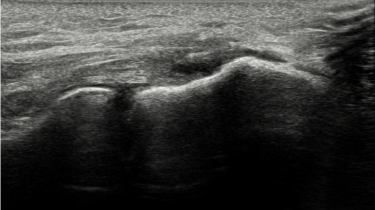

2022.11.16

골프엘보 치료 전 MRI

골프엘보 치료 후 MRI